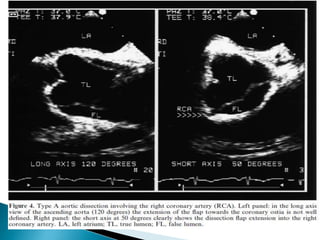

 Aortic dissection is a clinical emergency that is challenging to diagnose.

 TEE and CT angiography are the two most commonly employed imaging

modalities for aortic dissection.

 Multiple studies have demonstrated the high sensitivity and specificity of

both modalities for diagnosing type A dissections.

 The sensitivity and specificity of TEE have been reported as 90% to 100%

and 94% respectively .